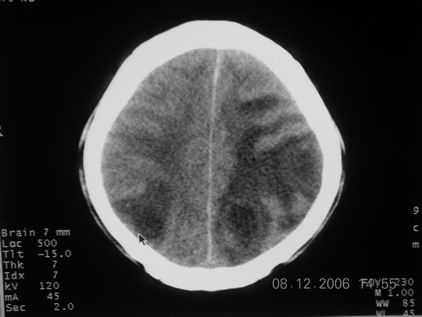

标题: CT11164:男,46岁,白血病患者,,大家看看. [打印本页]

标题: CT11164:男,46岁,白血病患者,,大家看看.

以前的片子,病史忘了,男,46岁,白血病患者,后来到中山二院诊断为

谁见过白血病中枢系统改变是怎么样的吗?

白血病脑浸润。

支持白血病脑浸润.

1 多发脑脓肿可能性大.>2 白血病浸润.

白血病脑浸润。没见过!但结合病史应首先考虑此病。

支持白血病脑浸润

结合病史考虑白血病脑浸润。

结合白血病病史,支持考虑白血病脑浸润。

结合病史考虑白血病脑浸润